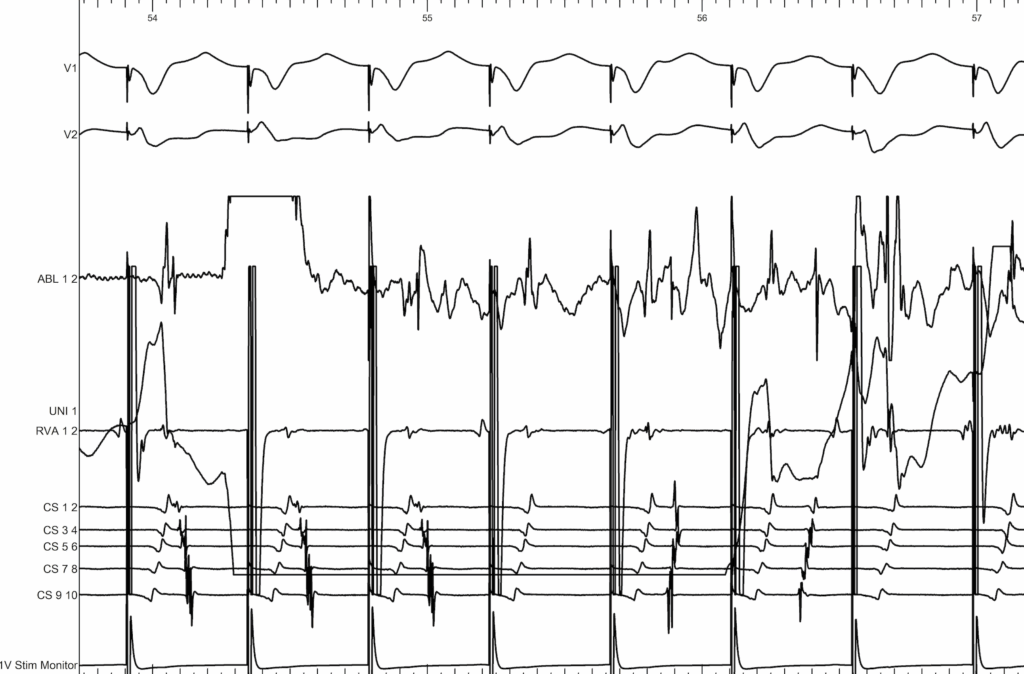

EP study showing a non-decremental, eccentric VA with earliest activation from CS1–2

We move toward the left side, and during ventricular pacing we look for VA fusion — which I see as a kind of ‘pyramidal’ pattern we need to identify. If we examine the signals carefully, the ventricular activation from CS9–10 travels upward and to the right toward the ablation catheter, while the atrial signal from CS9–10 travels upward and to the left. Both wavefronts converge toward the ablation catheter, where they fuse.

You can clearly see on the mapping, at the level of the ablation catheter, that there is a fusion between the atrial and ventricular signals.